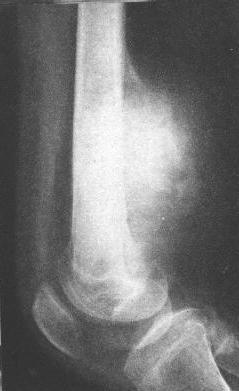

骨肉瘤(溶骨型)

胫骨骨肉瘤(溶骨型)。胫骨上端偏内侧骨松质虫蚀状骨破坏,局部骨皮质消失。

6.分化原始的肉瘤新骨生长很少,骨质破坏显著,成为以破骨为主的溶骨型骨肉瘤,其恶性程度一般较高,生长较迅速。实际上,多数病例为两者的混合型